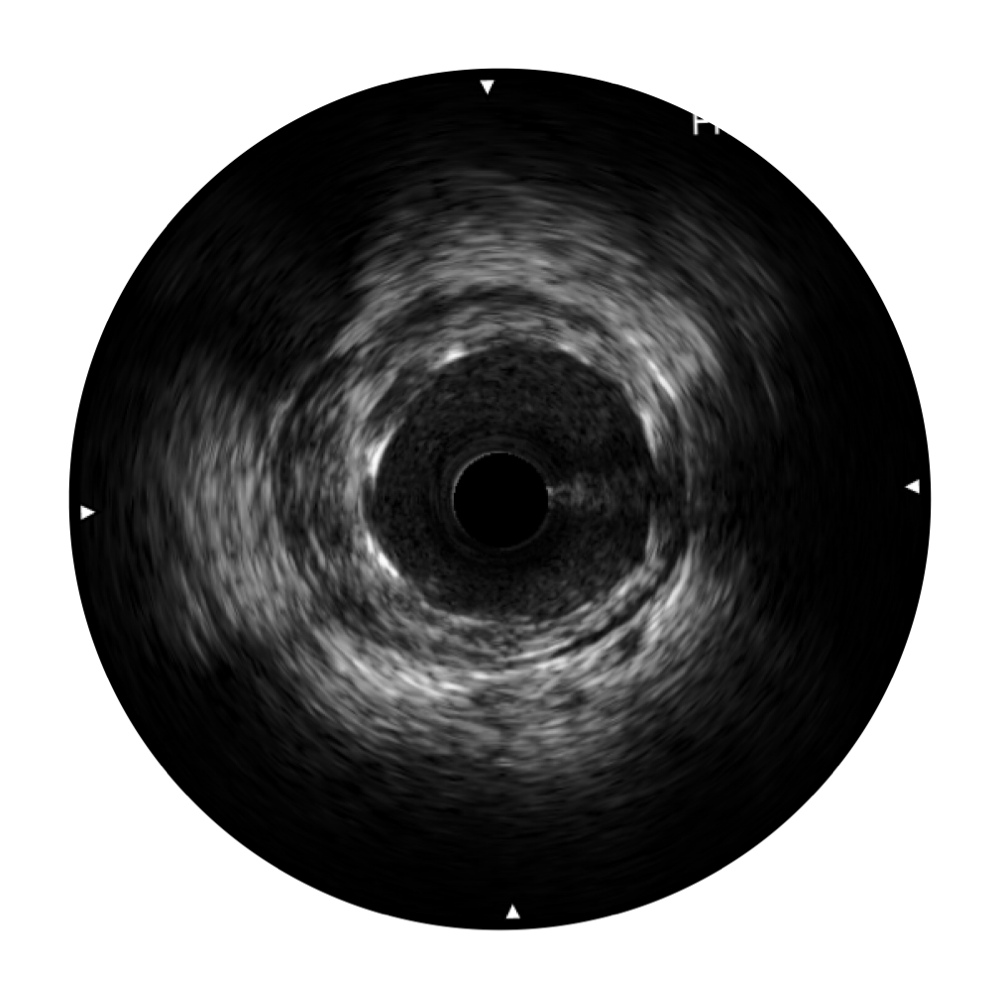

• milan米兰宽频IVUS图像

• 传统IVUS图像

对比传统IVUS导管成像,milan米兰宽频IVUS图像的近场支架梁显影更细腻,远场中膜外血管仍清晰可辨,兼顾远中近,兼顾分辨力与穿透深度